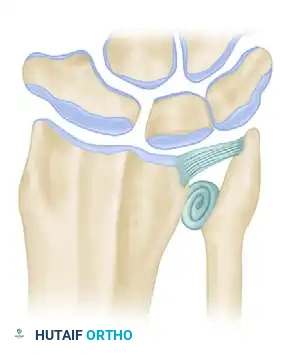

Figure 4 (Bowers B): Correction of impingement via soft tissue interposition. A tendon ball is sutured into the radioulnar defect, acting as a biological buffer.